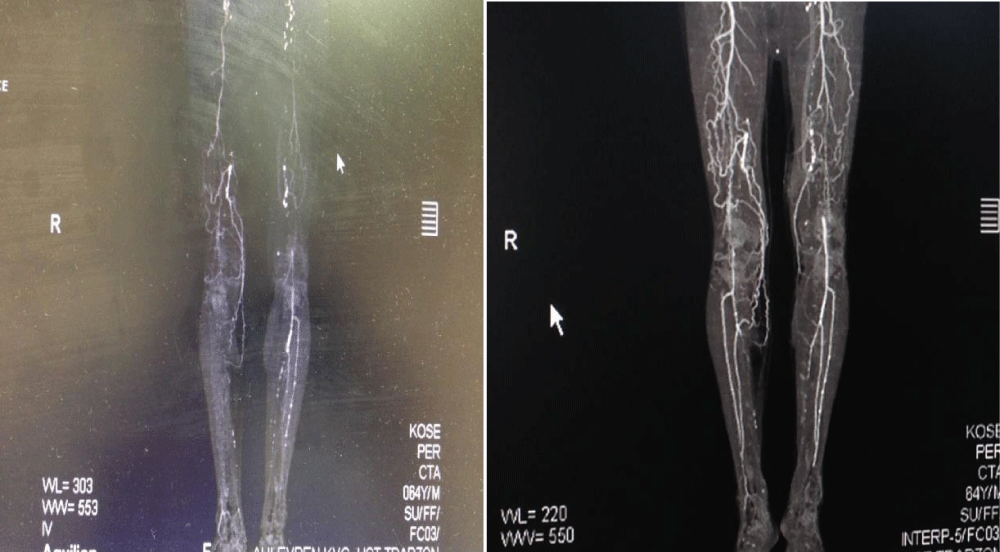

Download Image

Figure 4: Exemplary CT angiographic images preoperatively and at postoperative month 6.

Figure 5: Exemplary CT angiographic images preoperatively and at postoperative month 6.

Following intra-arterial + intramuscular stem cell transplantation, a significant increase in ABI was noted, together with significant growth in pain-free maximum walking distance and mild improvement in skin saturation index. In those with extremity wounds, the wound healing process also appeared to be accelerated. Tomographic angiography at 6 months showed the formation of small new vessels as a result of angiogenesis in one-third of the patients. Of the 8 patients with critical ischemia that could require amputation, major amputation was performed in 2, and minor amputation in 1. The two patients who required major amputation were those who had undergone therapy with stem cells of adipose origin. A patient with a minor amputation had received stem cells of bone marrow origin.